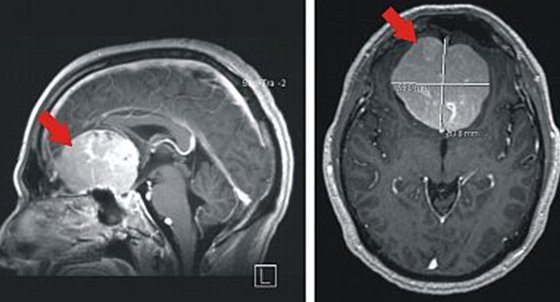

Meningeome

Diese grundsätzlich gutartigen Tumore gehen von der harten Hirnhaut (Dura mater) aus und wachsen verdrängend gegen das Gehirn. Selten wachsen sie auch in das Hirngewebe ein.

Da Meningeome in der Regel langsam wachsen können sie eine beträchtliche Größe erreichen, bevor sie Symptome erzeugen. Diese Symptome sind häufig unspezifisch. Meningeome sind aber auch dafür bekannt, epileptische Anfälle auszulösen, so dass in einigen Fällen aufgrund eines Krampfereignisses die Diagnostik erfolgt.